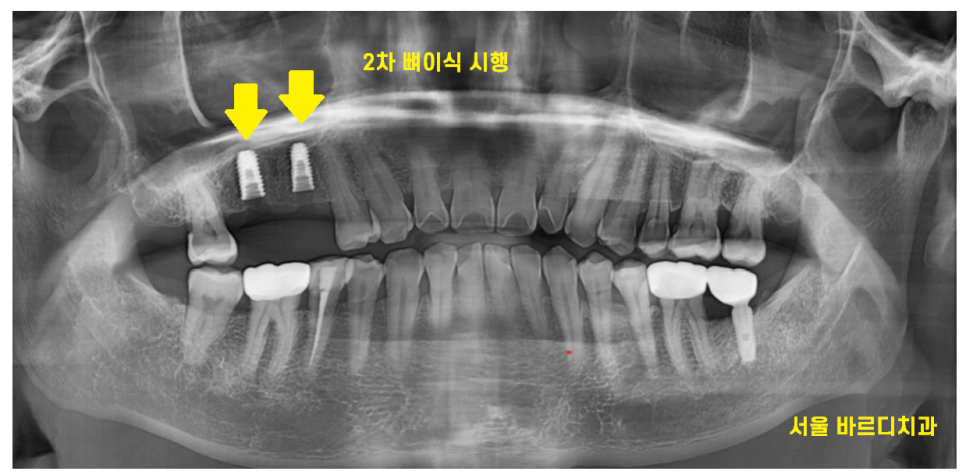

23.09.15

처음 고덕동 임플란트를 위해 내원하신 뒤

6개월이 지나서 수술하게 되었습니다.

발치하면서 1차적으로 뼈를 이식해두긴 했지만

워낙 방대한 양의 뼈가 없어서

한번 더 상악동 구조물을 올리고

뼈이식을 진행했습니다.

(뼈이식만 두번~~!!)